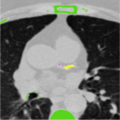

A semi-automated method to segment and identify calcium plaques in coronary arteries in order to calculate the Agatston score (a measurement used to determine coronary artery disease and treatment).